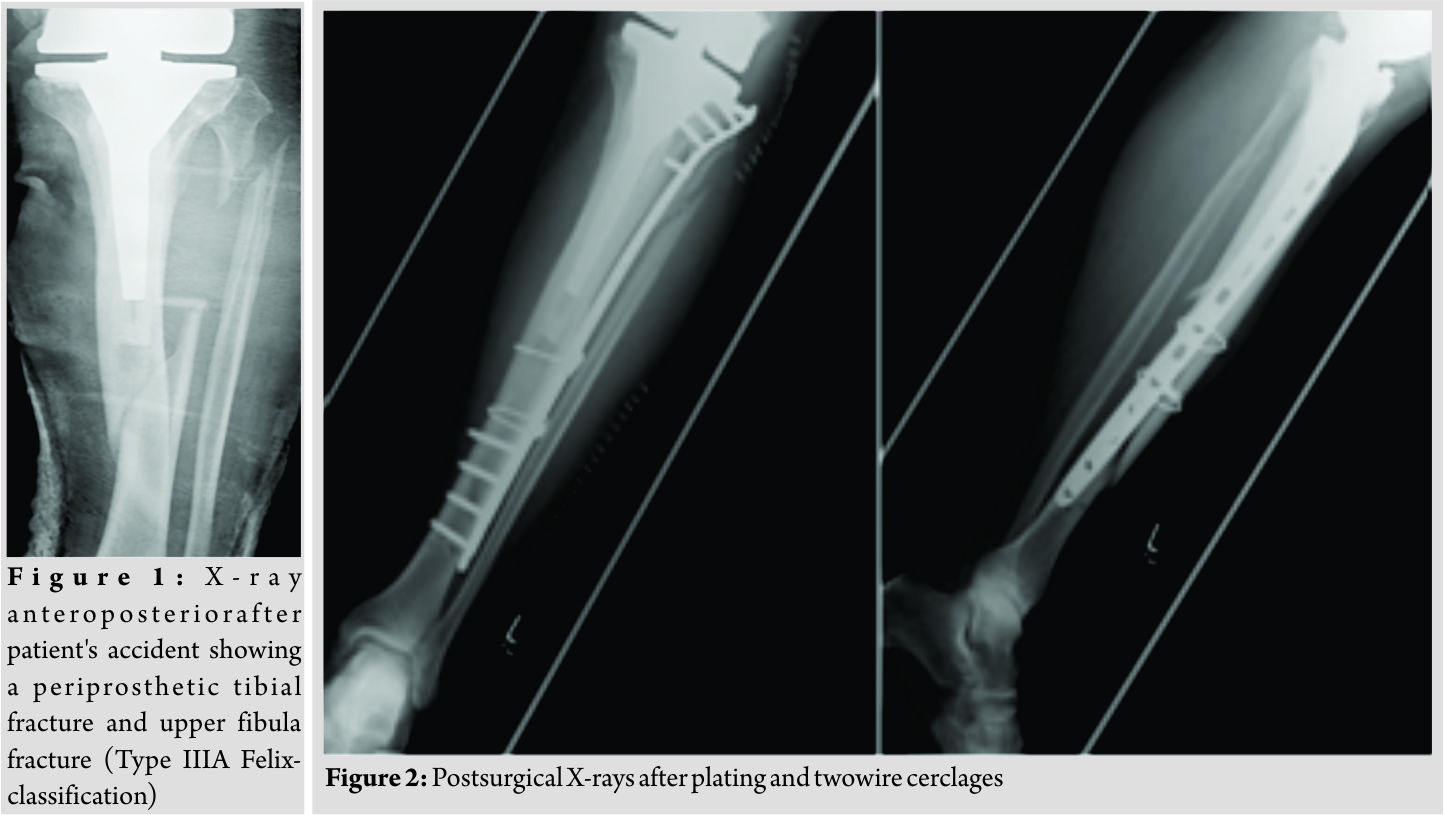

The present case report concerns a 69-year-old male patient who was admitted to the department of traumatology and orthopaedic surgery. The patient was admitted in February 2014 after he had a bicycle accident. Standardized X-rays of the affected leg showed a periprosthetic fracture of the tibia and an upper fracture of the fibula which was negligible (Felix [Mayo] classification Type IIIa, Fig. 1). In the medical history of the left knee, the patient underwent primary TKA in May 2004 due to osteoarthritis. Furthermore, revision surgery was performed with the implant changed to a constrained TKA system due to an aseptic loosening in October 2013. The patient reported a satisfying functional and subjective outcome of his left knee before the accident. We saw the patient with a painful leg but without any clinical signs of compartment syndrome. Diagnostics and pre-operative planning were completed with a computed tomography scan and laboratory counts. Primary care included stabilization with a knee joint bridging external fixator and a puncture of the knee. After soft tissue conditions were improved the external fixator was removed, andthe tibial fracture was stabilized with a plate and two wire cerclages (less invasive stabilization system [LISS], 13 screw holes, Synthes GmbH, Umkirchbei Freiburg, Germany) (Fig. 2).